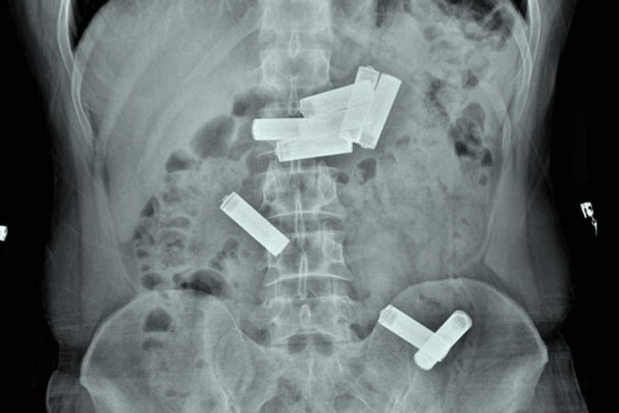

Gaziantep Kapalı Cezaevi'nde kalan mahkum D.K., geçen hafta içerisinde koğuşunda rahatsızlanınca Dr. Ersin Devlet Hastanesi'ne götürüldü. Acil serviste muayenesi yapıldıktan sonra çekilen röntgende D.K.'nin midesinde 8 kalem pil olduğu saptanınca Endoskopi Servisi'ne sevk edildi. Gastroenteroloji uzmanı doktor Ahmet Yağbasan başkanlığındaki ekip, yaptığı çalışma ile D.K.'nin midesindeki pillerin birisini çıkardı. Uzmanlar, mahkumun midesindeki diğer 7 pilin müdahale yapılarak çıkarılmasının dokulara zarar vereceğini belirleyince takip altında doğal yollardan çıkarılması kararını verdi. Bunun üzerine servise yatırılan D.K., 2 gün sonra midesindeki pilleri doğal yollarla vücudundan çıkardı.

"Vaka bize cezaevinden karın ağrısı şikayetiyle getirildi. Acil serviste çekilen röntgende midesinde kalem pillerin olduğunu belirledik. Bunun üzerine hastayı endoskopi ünitesine aldık. Midede 8 pil olduğunu gördük ve bunları özel aletlerle çıkarmayı denedik. Yaptığımız müdahale ile birini çıkardık ama diğerlerinin pozisyonu uygun olmadığı için çıkaramadık. Pillerin içindeki kimyasal maddelerden dolayı doku hasarına yol açabileceğini kanaat getirerek, hastanın diğer 7 pili takip altında doğal yollardan çıkarmasını kararlaştırdık. Serviste yatan hastamız 2 gün sonra pilleri doğal yollardan çıkarmış oldu."